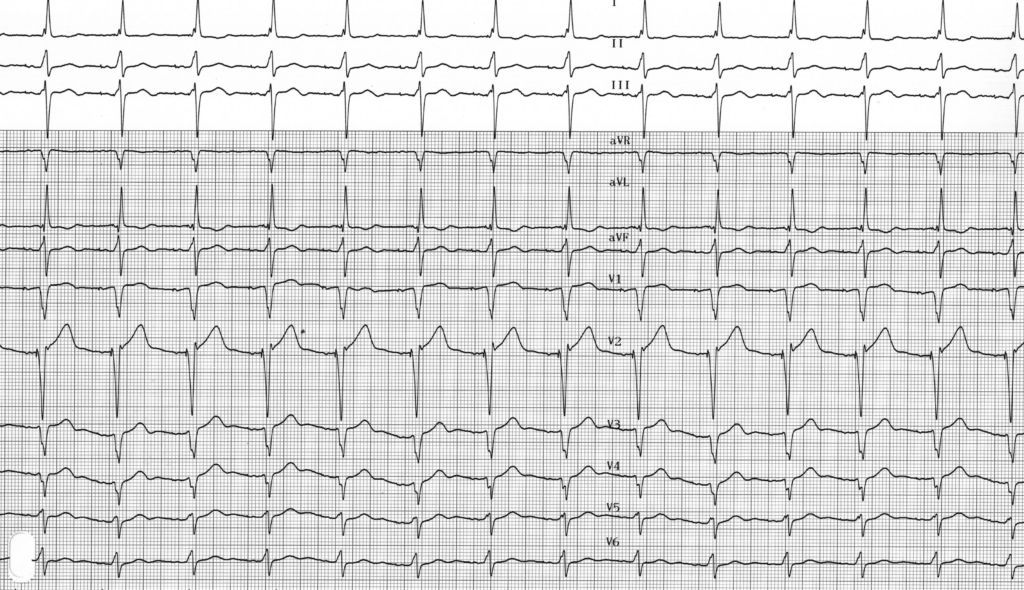

Tracé 4.6: Stimulation unipolaire versus stimulation bipolaire

ECG description

Stimulation atriale et ventriculaire en mode bipolaire (petite amplitude des stimuli atriaux et ventriculaires qui sont parfois non identifiables);